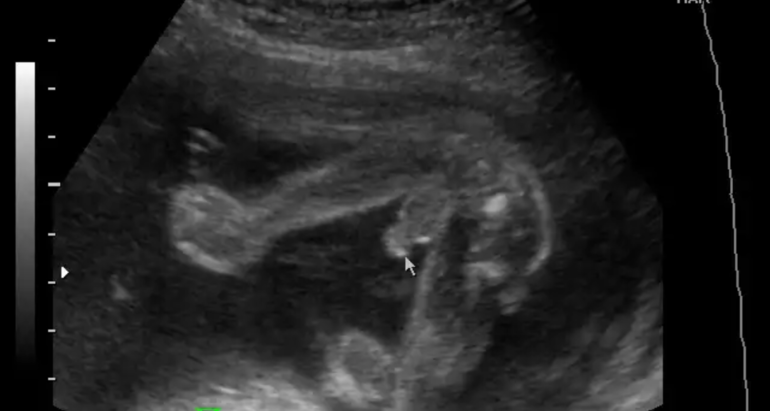

Слева - девочка, а справа мальчик (пенис зажат, но яички не спутаешь ни с чем), просто ноги поджал малыш.

Ракурсы не самые удачные)мне когда показывали то там всё было чётко и ясно,у сына такое внушительное хозяйство было,ни с чем не спутать,а у дочки сейчас всё так аккуратненько,прям персик))но если точно знать что разнополые,то мальчик справа,хотя там всё размыто и непонятно,слева девчушка однозначно!

На данных изображениях не вижу. Всегда когда видела писюн на узи он торчал прям оч сильно. Со всех ракурсов))))

По мне, так две одинаковые попы.

Делая скидку на позу, хотелось бы, конечно, чтобы справа девочка была)))